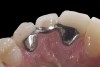

Six years later, the patient was in his fourth year of college when he finally returned for implant placement (Figure 6). Interestingly, the provisional bridge had not come loose since it was bonded, even though the patient had a nail biting habit and had fractured most of the resin-based composite on the central incisors. He had also failed to wear his retainer, and as a result, the upper left lateral incisor had rotated slightly (Figure 6). In the right lateral incisor site, there was a horizontal deficiency in the bone and overlying soft tissue. A cone-beam computed tomography (CBCT) image was taken, and the area was evaluated for implant placement. There was enough native bone to place a 3 mm implant, but a connective tissue graft was needed to rebuild the deficient ridge. Unfortunately, when the patient presented for implant placement, it was during a holiday break from school and he needed to study. Therefore, the patient did not want to simultaneously augment with a connective tissue graft at the time of implant placement due to the pain associated with treatment. A 3.0 x 10 mm Astra Tech implant was placed, and the resin-bonded bridge was rebonded, utilizing the CoJet Silica, salinization, and the same dual-cured resin cement. Four months later, the patient returned for the connective tissue graft (Figure 7). The bridge was removed, the graft was performed utilizing a tunnel technique, and the bridge was rebonded as described earlier (Figure 8). After another four months, the patient returned during a two-week break. At this time, the implant was exposed, the tissue was manipulated with provisionals, and the final restorative work was completed (Figure 10 and Figure 11).

(7.) Resin-bonded bridge after removal, implant placement, and bridge recementation.

Figure 7

(8.) Resin-bonded bridge removed and CT graft completed. Bridge recemented once more. Note reduction in cervical area of pontic.

Figure 8